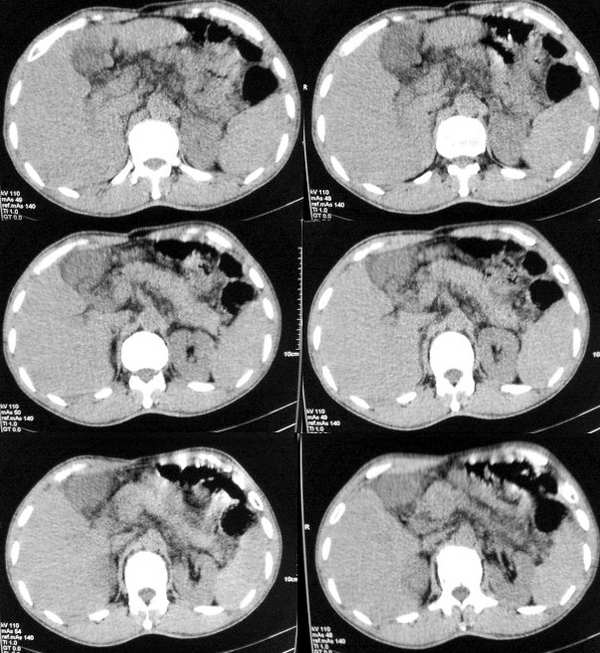

以下是引用butterylf在2005-12-21 19:10:00的发言:[br]我扫出来的图像都是这样的,窗宽窗位我参考了别的医院的啊,可是为什么我扫出来的图像质量不好,不好意思,是从显示器上拍的,而且还是用手机拍的,我不知道其他还能有什么方法拍啊!![br]病人是男性,41岁,[br]另外mas怎么调,不是不同的部位都要重新调过吧,?[br][br][br]对了,各位老师,我想问一个问题,我现在扫描片子打不出来了,这是为什么?ct已经传送过去了,可是激光打印就是出不来啊,打印机上总是显示close lower cover?这是为什么啊?